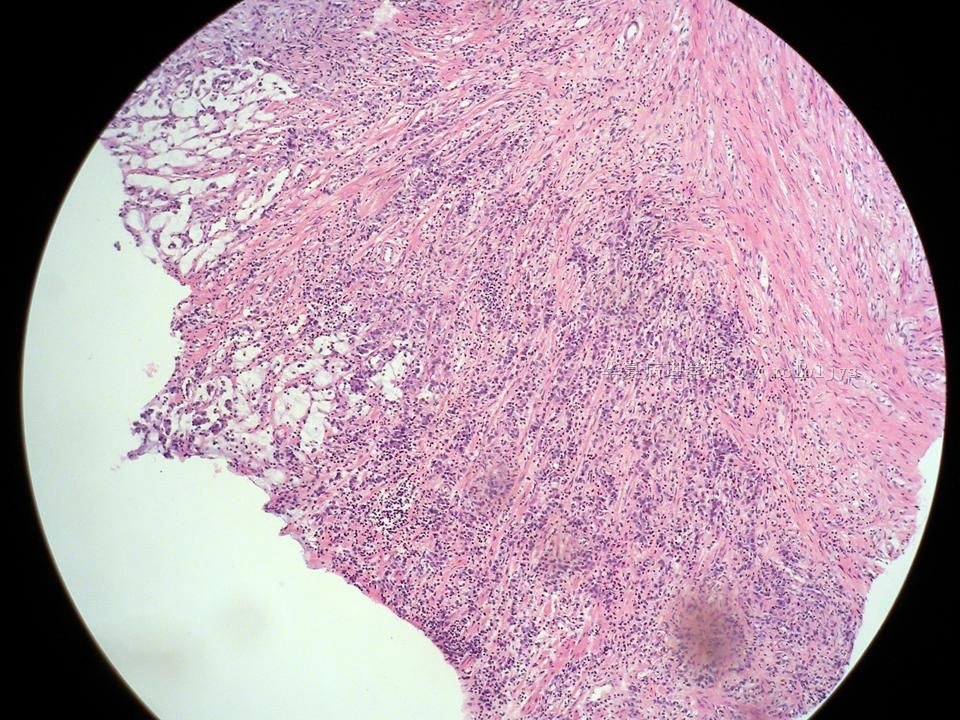

腺癌。 另外我想请教老师该病例如何取材? 此镜下表现取材为何处? 谢谢老师!!! |

此病例取材的思路为:1.按幽门梗阻取材,证明梗阻区主要成分为胶原纤维;2.按非幽门梗阻取材,期望看到其他病变。

做冰冻时我们就在幽门增厚区切面部分灰白区取了两块,从粘膜面到浆膜面。直到冰冻切片出来,我们才意识到此例非幽门梗阻,而是腺癌!尽管肉眼上不典型!

此例提示,胃上皮性恶性肿瘤,肉眼表现多种多样,许多肉眼形态具有欺骗性,故取材时要多点心眼!不要怕麻烦,不要相信经验,要相信事实!毕竟我们对自然并不完全了解!